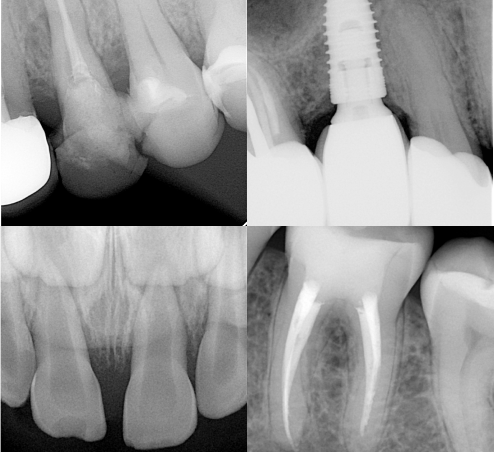

Внутрішньоротова рентгенографія

Цей тип дослідження передбачає отримання зображення невеликої ділянки щелепи на плівку або сенсор радіовізіографа (RVG). Інколи цей метод називають прицільним знімком. Його перевагами є доступність і найменша доза опромінення у порівнянні з іншими видами досліджень. Серед недоліків: певний дискомфорт для пацієнта (при розташуванні сенсора чи плівки в ротовій порожнині) та виражене погіршення якості діагностичної інформації від найменших помилок під час виконання дослідження.